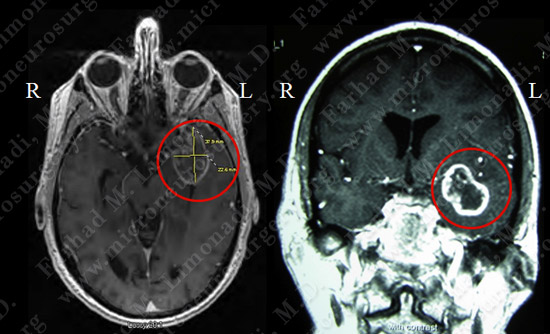

- Patient is a 60+ year old gentleman who was experiencing funny smells lasting a few minutes (olfactory hallucination secondary to uncinate seizure).

- He underwent a thorough evaluation by his neurologist including an MRI scan of the brain.

Imaging